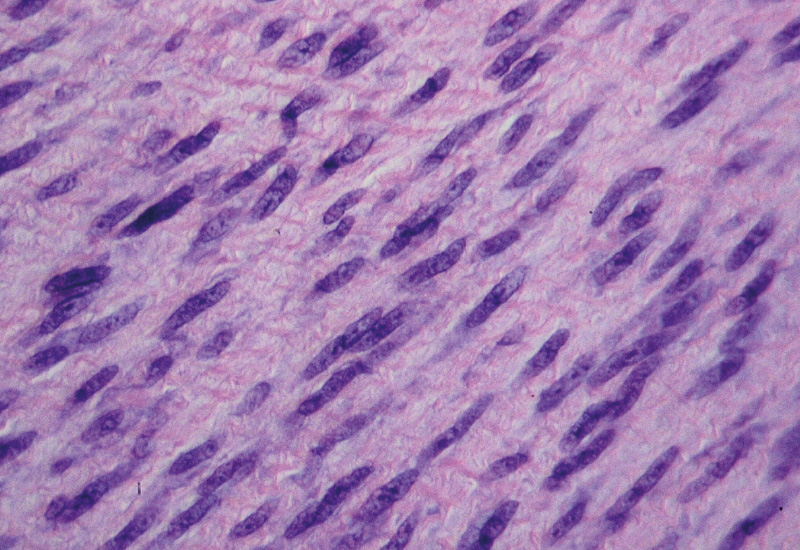

Laborstudien hatten gezeigt, dass der M. Dupuytren eine lokale entzündliche Störung ist. Die Entwicklung und Erhaltung von Myofibroblasten (die für die Ablagerung und Kontraktion der Kollagenmatrix verantwortlich sind) ist abhängig von der Sekretion geringer TNF-Mengen durch lokale Immunzellen, einschließlich Makrophagen und Mastzellen. In einer Phase-IIa-Dosisfindungsstudie hatte 40 mg Adalimumab in 0,4 ml die beste Wirksamkeit gezeigt und es konnte eine Downregulation von Myofibroblasten-Markern nachgewiesen werden.